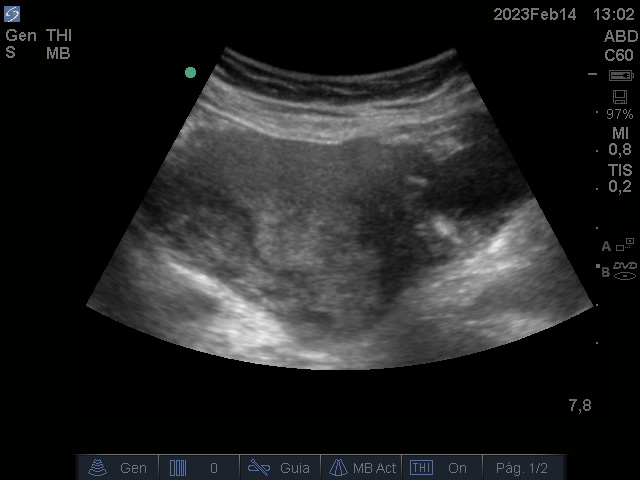

Se realiza ecografía renal y vesical en Consulta de médico de Cabecera

Hallazgos ecográficos

Útero aumentado de tamaño heterogéneo, con áreas sólido quísticas de bordes irregulares.